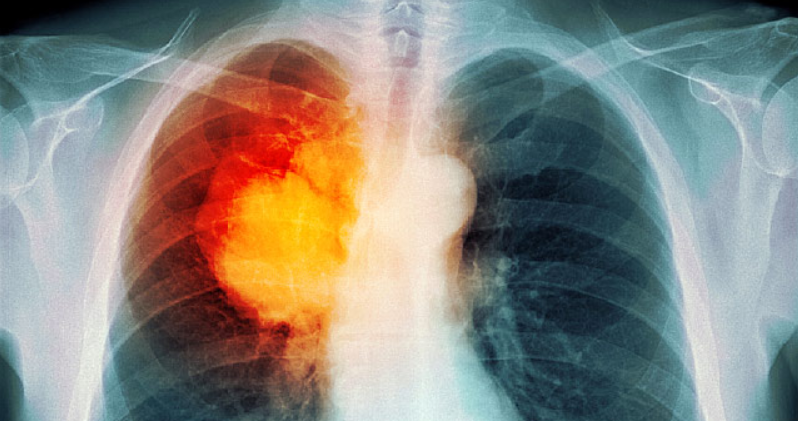

안녕하세요 아무 이유가 없는데 허리 통증을 느끼신다면, 여러 가지를 생각할 수 있습니다. 그러나 너무 단순하게 생각하지는 마세요. 허리 통증은 폐암과 연관이 있다는 결과가 있습니다. 담배를 피우시는 분이시라면 허리가 이유 없이 아프다면, 한 번쯤은 병원을 찾아가서 정밀검사를 해보는 것도 괜찮은 방법이겠습니다. 그럼 지금부터 허리 통증과 폐암초기증상의 연관성을 다루어보도록 하겠습니다.

통증에는 여러가지 증상을 구분하는 특징이 있습니다. 사람들이 폐암으로 허리 통증을 경험하거나 심지어 첫 증상으로 허리 통증을 경험하는 사람들도 있습니다.

허리와 폐를 연결하는 것처럼 보일 수도 있지만, 특유의 특징을 정의하는 기능이 있습니다. 그 중에서도 가장 많이 경험하는 통증의 위치와 유형이 전형적인 전형적인 만성 통증과 다릅니다. 폐암 환자의 약 25 %가 허리 통증을 증상으로보고 할 것이라고 한다.